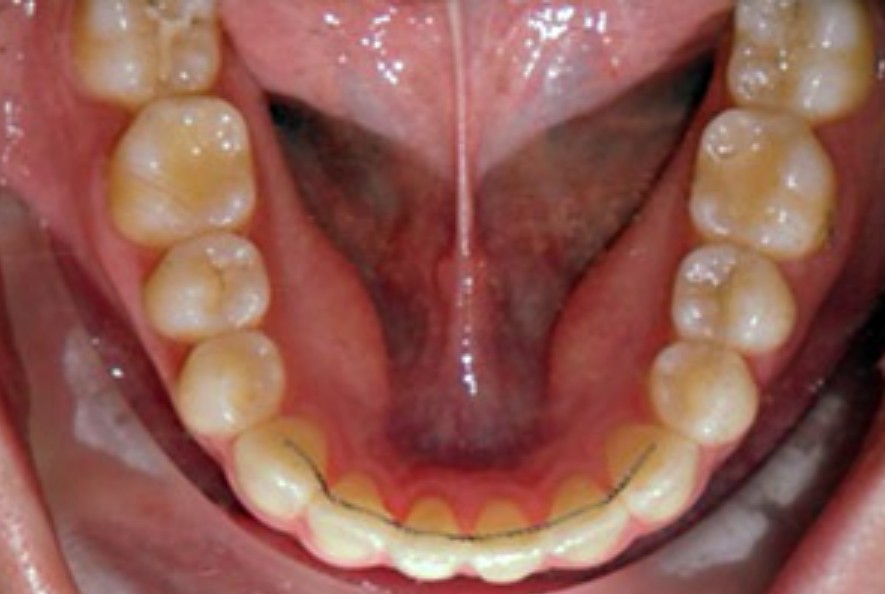

치아교정이 끝나고 장치를 제거하면 제거하는 그 순간 부터 치아가 예전으로 돌아갑니다. 즉 유지장치를 안하면 예전처럼 다시 비뚤비뚤해지니 약간은 불편하더라도 유지장치는 무조건 하는게 좋습니다.

교정장치 했을 때 만큼 많이 조심할 필요는없고 앞니쪽으로 아이스크림을 앙 물어먹거나 앞니쪽으로 단단한건 안드시는게 좋습니다. 유지장치가 앞니쪽에만 붙어있으니 어금니쪽으로 드시는게 좋겠죠???

유지장치는 항상 떨어지지 않도록 주의해주세요!!!!